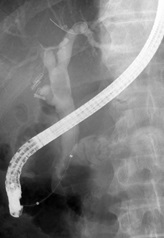

- ERCP・・・総肝胆結石や胆管腫瘍に対しての精査・処置

EPLBD |